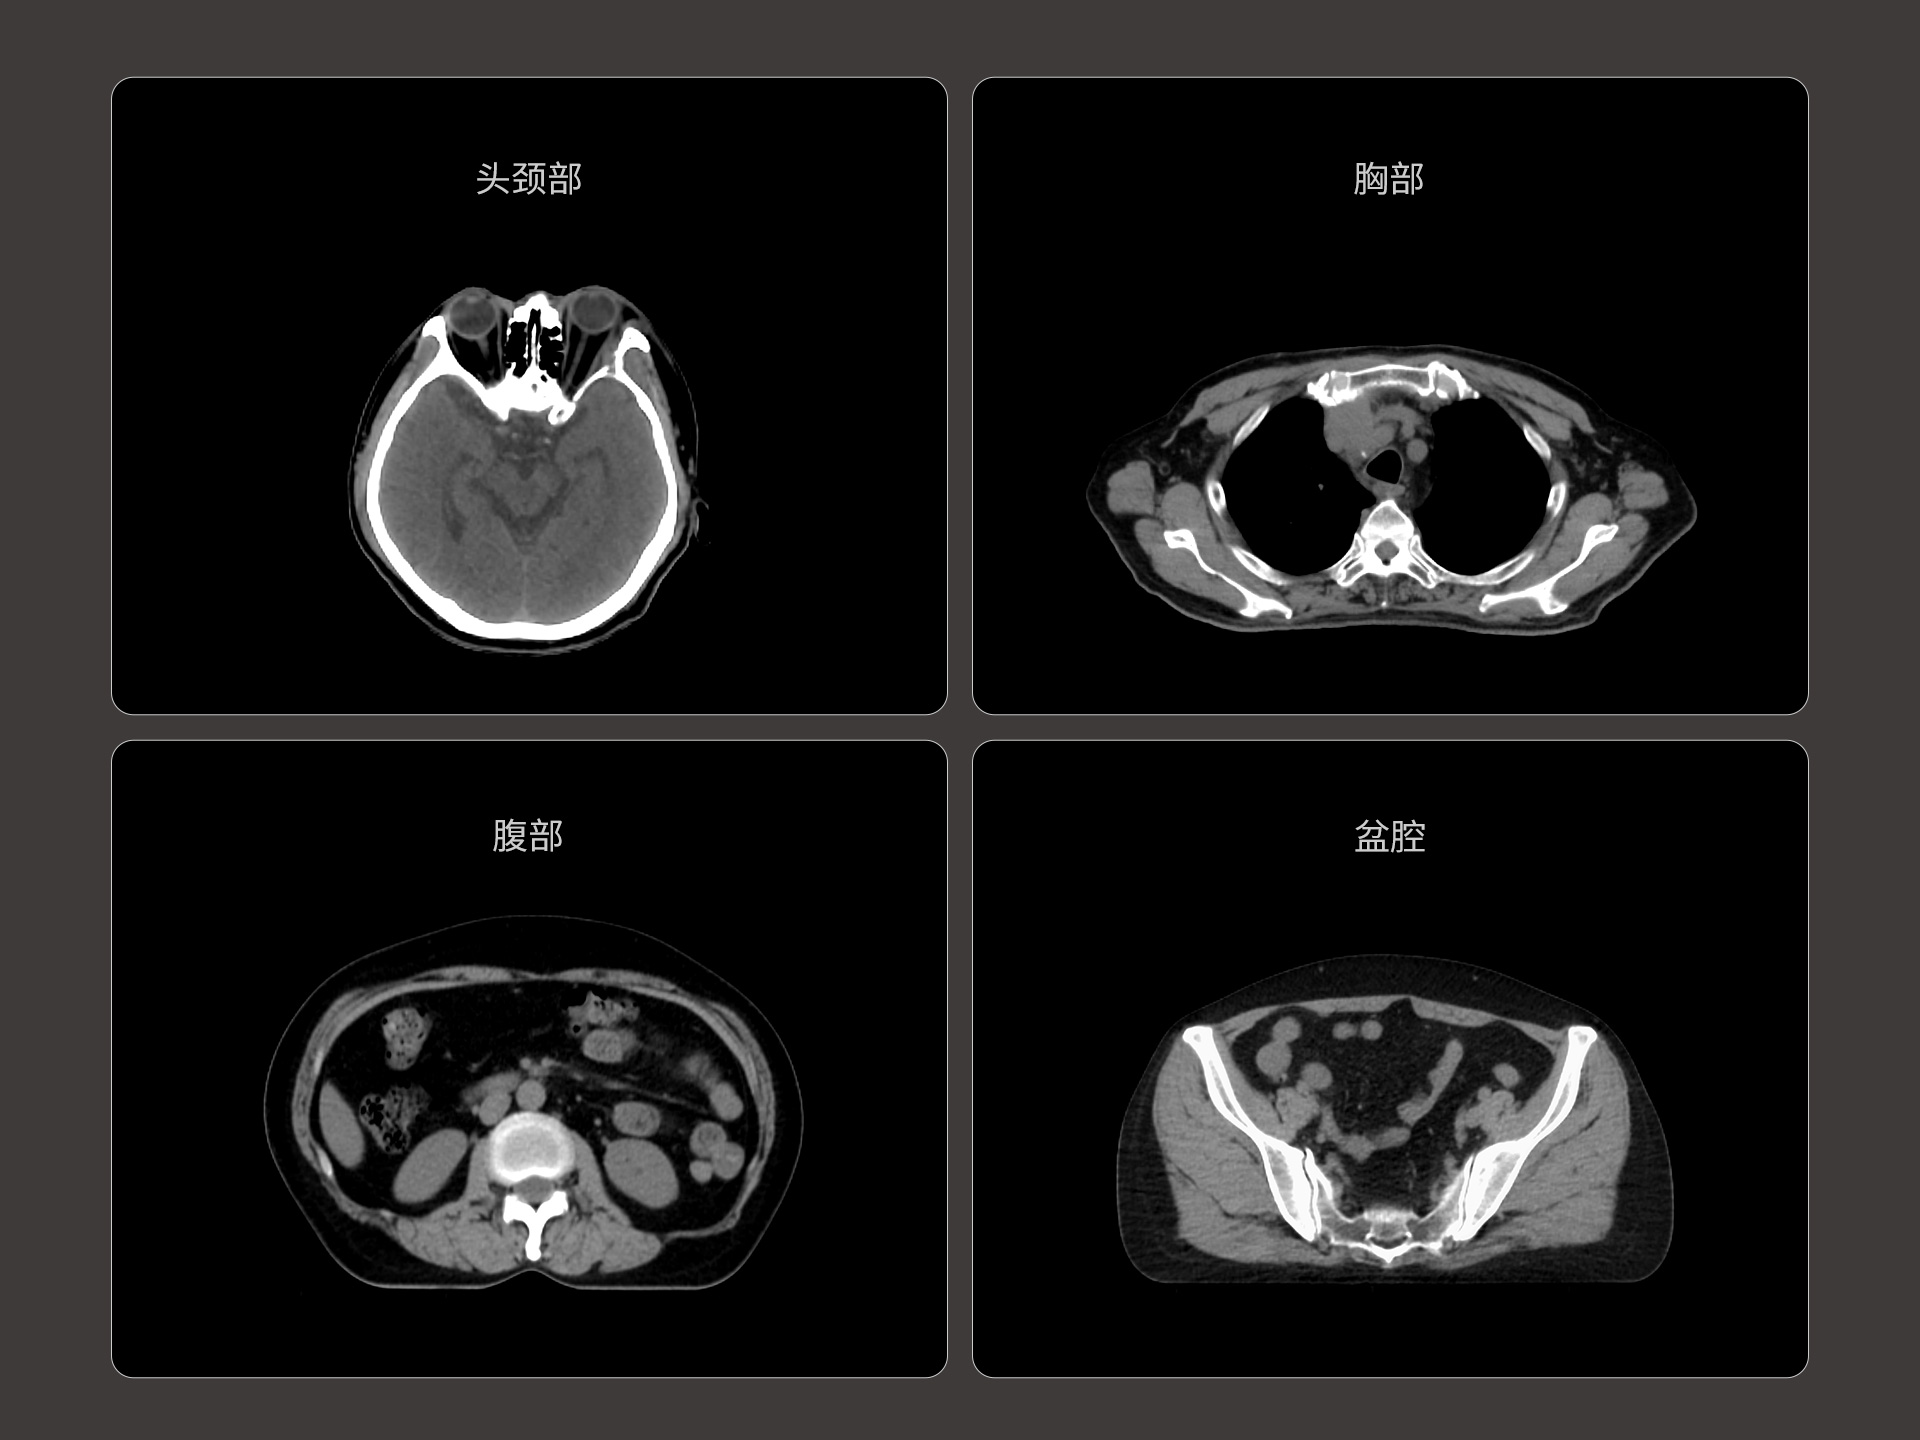

支持CT、MR、PET多模态影像及全身100+器官勾画模型,准确度高、分割速度快、重现性好,提高临床勾画效率与一致性。

亚秒级自动勾画